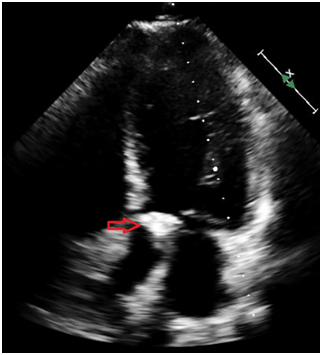

A 31-year-old Caucasian man presented to the hospital with 4day-history of left upper quadrant abdominal pain and left sided pleurisy. He had recently failed therapy for chronic HCV mono-infection, genotype 1a, with fibrosis score of F0. He admits to using intravenous recreational drugs. Vital signs were normal except for heart rate of 130/min. The abdomen was tender in the left upper abdominal quadrant with no of peritoneal irritation. Initial blood investigations revealed leukocytosis of 21.3x103/µl with normal renal function and liver enzymes. Computed tomography of the abdomen with IV contrast showed a large splenic infarct (Figure 1). He had no recent abdominal trauma or abdominal surgery. Streptococcus constellatus was cultivated from two sets of blood cultures on day three. Comprehensive workup excluded mononucleosis, pancreatic disorders, HIV, autoimmune/collagen vascular disease, sickle hemoglobinopathies, malignant hematologic disorders (normal peripheral blood smear, SPEP and flow cytometry), hepercoagulable state (normal protein C or protein S; normal lupus anticoagulant, factor V, prothrombin). Patient had no signs of ARDS, sepsis, septic shock or toxic shock syndrome. Patient no recent cardiac catheterization (angiographic embolization), sclerotherapy of esophageal varices, abdominal surgery (pancreatectomy, or liver transplant), vasopressin infusion, or embolization for splenic hemorrhage. Echocardiogram showed the presence of 2.5x1.5cm2 vegetation of the aortic valve with perforation, severe regurgitation and aortic root abscess (Figure 2). Magnetic resonance imaging (MRI) of the brain showed numerous brain abscesses, without mass effect or midline shift. This case was complex and Duke’s criteria were used to make the diagnosis of IE. The patient received aortic valve replacement and his post-operative course was uneventful. Administration of ertapenem was continued for 8 weeks. The patient had full neurological recovery and repeat MRI of the brain showed complete resolution of the abscesses. Follow-up echocardiogram showed no thrombosis or vegetation of the bioprosthetic valve.

Figure 2A) Echocardiogram showed the presence of 2.5x1.5cm2 vegetation of the aortic valve.